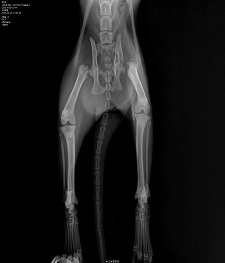

엑스레이를 찍고 심각한 얼굴로 원장님께서 진료실로 부르셨다.

" 엑스레이상.. 뒷다리 모두 골절 골반뼈 골절 심지어 온 뼈가 잔금 투성입니다.. 복주 학대 고양이 맞죠?..

너무 심각한 상태이고.. 위에는 오랫동안 아무것도 먹지 못해 비어있고 탈수도 너무 심합니다."

복주는 한번의 수술로 끝날 일이 아니라 하였다..

적어도 3차 수술까지 진행을 해야 하고 큰 수술인지라 잦은 마취로 인해 텀을 두고 수술진행을 해야한다고 한다.

그리고 뒷다리 하나는 부러진 뼈와 인대 파손이 심해 절단을 고려 할수도 있는 상태라 하셨다.

5개월 정도 밖에 되지 않아 어린 고양이가 큰 수술을 다 견뎌낼지도 걱정이라고 하심에 눈물이 왈칵 쏟아졌다.